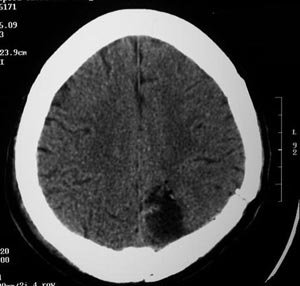

Figura 57 - Ressonância nuclear magnética pós-operatória mostrando adequada ressecção da lesão.

Figura 60- Ressonância nuclear magnética pós-operatória mostrando adequada ressecção da lesão.